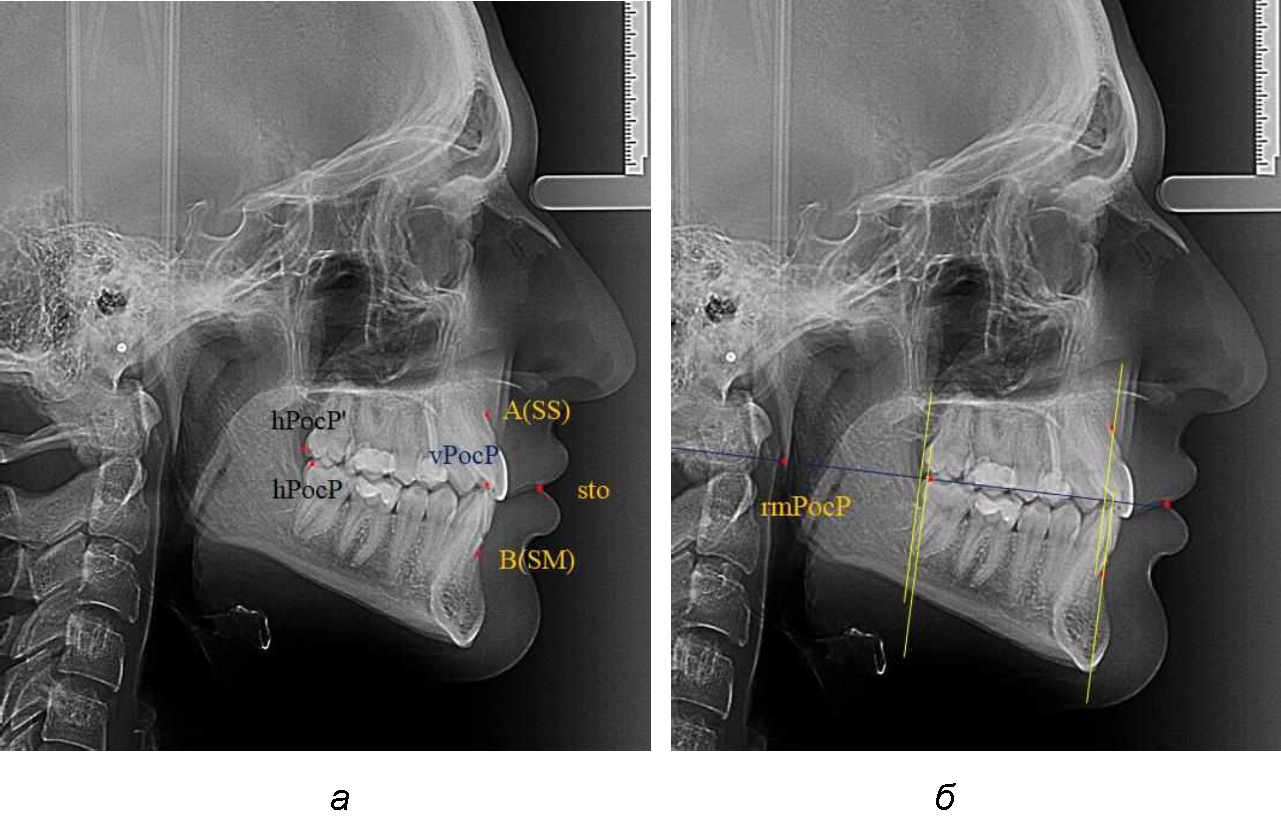

При анализе рентгенограмм, было отмечено, что на 26 снимках из 58 [(44,83 ± 6,53) %] отмечалась нормопозиция верхней челюсти. При этом средняя величина лицевого угла (ANSe) составила (85,04 ± 0,56)°, и пациенты были отнесены к 1-й группе 1-й подгруппе. Антепозиция верхней челюсти была отмечена на 20 те-лерентгенограммах [(34,483 ± 6,24) %], при этом величина лицевого угла составляла (89,12 ± 0,62)°. Ретропозиция была отмечена на 12 рентгенограммах [(20,69 ± 5,32) %], а средняя величина лицевого угла составляла (80,21 ± 0,48)°.

При всех вариантах положения верхней челюсти, было отмечено, что альвеолярно-денталь-ные размеры верхних зубо-челюстных дуг были близки по значению к аналогичным размерам нижней челюсти и разница в размерах не превышала 1,0–1,5 мм, а средняя величина различия показателей составляла (1,07 ± 0,54) мм.

Расстояние от конструируемой точки окклюзионной плоскости на ветви челюсти («rmРOcP») до апикальных точек Downs на обеих челюстях также коррелировало между собой, и средняя величина различия показателей составляла (1,23 ± 0,69) мм. Проекция нижней апикальной точки на окклюзионную линию, как правило, располагалась несколько кпереди проекции верхней апикальной точки, на величину около 1 мм, что соответствовало оптимальным данным Wits-анализа.

Аналогичное расстояние было отмечено и при расположении дистальных окклюзионных точек верхней и нижней челюсти (рис. 2).

Рис. 2. Положение апикальных точек и челюстей при нормопозиции (а), антепозиции (б) и ретропозиции (в) верхней челюсти